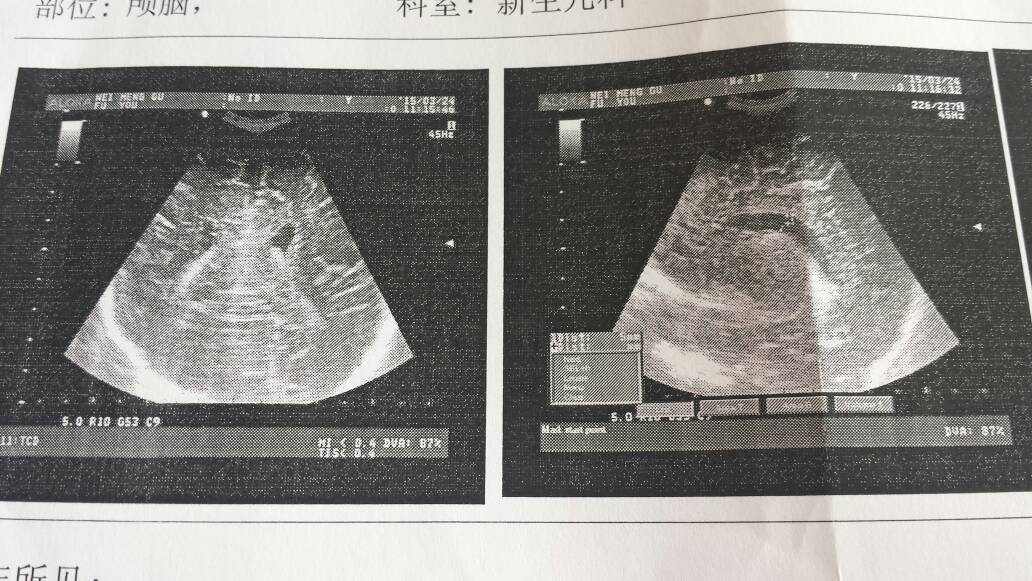

早产儿现四个月,左右侧脑出血二级,右侧脑轻度扩大纵经六毫米,左侧脑室纵经5毫米,严重吗?有什么方法 早产儿现四个月,左右侧脑出血二级,右侧脑轻度扩大纵经六毫米,左侧脑室纵经5毫米,严重吗?有什么方法缓解治愈? 点击展开 匿名用户 2015-03-25 12:28 为您推荐: 其他回答 你同事孩子现在情况好不? 匿名用户 2016-05-01 10:02 有些孩子是这样的 我有个同事他家孩子就是这样 现在9岁了 匿名用户 2015-03-26 11:46 相关问题 早产儿三十六周脑出血严重吗 早产儿中度脑出血会不会影响以后的发育 我儿子35周+6天!早产儿脑出血严不严重?